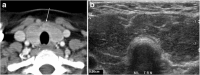

Focal and diffuse thyroid abnormalities are commonly encountered during the interpretation of computed tomography (CT) exams performed for various clinical purposes. These findings can often lead to a diagnostic dilemma, as the CT reflects the nonspecific appearances. Ultrasound (US) examination has a superior spatial resolution and is considered the modality of choice for thyroid evaluation. Nevertheless, CT detects incidental thyroid nodules (ITNs) and plays an important role in the evaluation of thyroid cancer. In this pictorial review, we cover a wide spectrum of common and uncommon, incidental and non-incidental thyroid findings from CT scans. We also discuss the most common incidental thyroid findings, best practices for their evaluation, and recommendations for their management. In addition, we explore the role of imaging in the assessment of thyroid carcinoma (before and after treatment) and preoperative thyroid goiter, as well as localization of ectopic and congenital thyroid tissue.